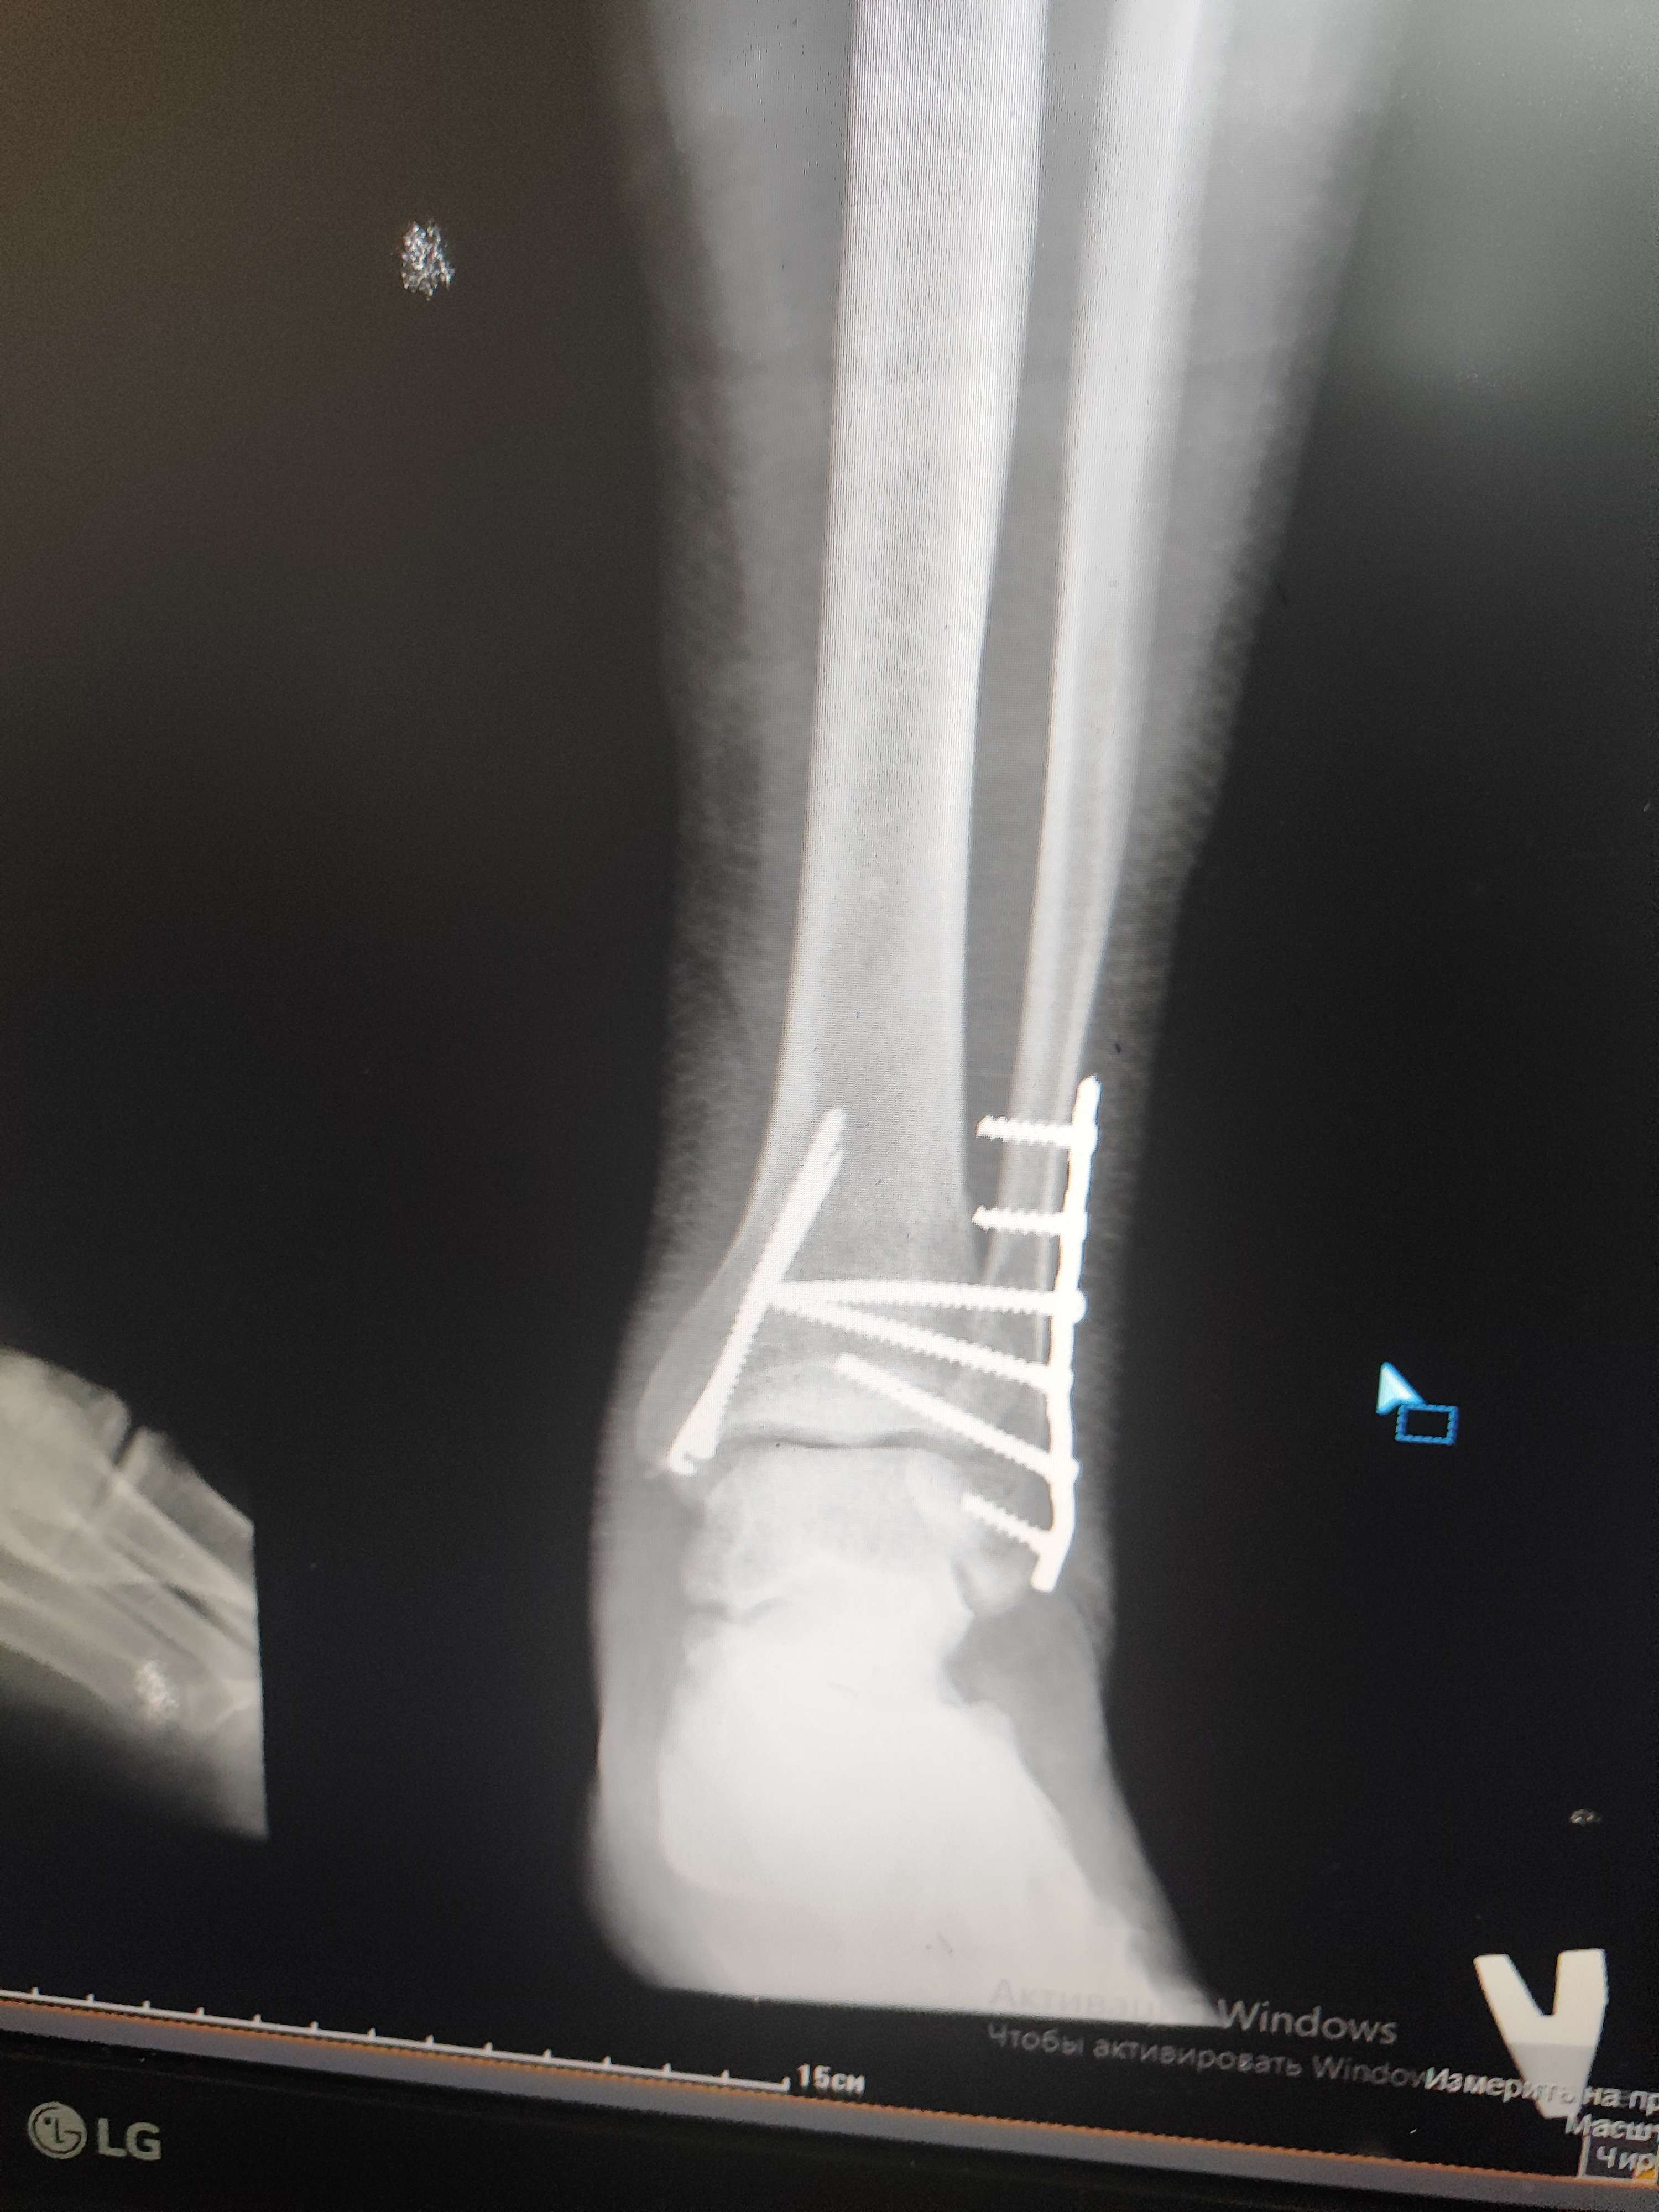

Здравствуйте, прошу посмотреть мои снимки. Что может быть не правильно? Каков исход данной операции? На данный момент прошло 3-мес. Вопрос по тыльному сгибанию стопы стоит остро потому как его практически нет,есть только 90'гр.

Нахожусь в стране с ограниченным количеством медучереждений и врачей, поэтому Ваше мнение будет очень ценным для меня

Поэтой одной проекции особых проблем не вино. Может, что-то не так на профильном снимке. Движения надо разрабатвать в любом случае.